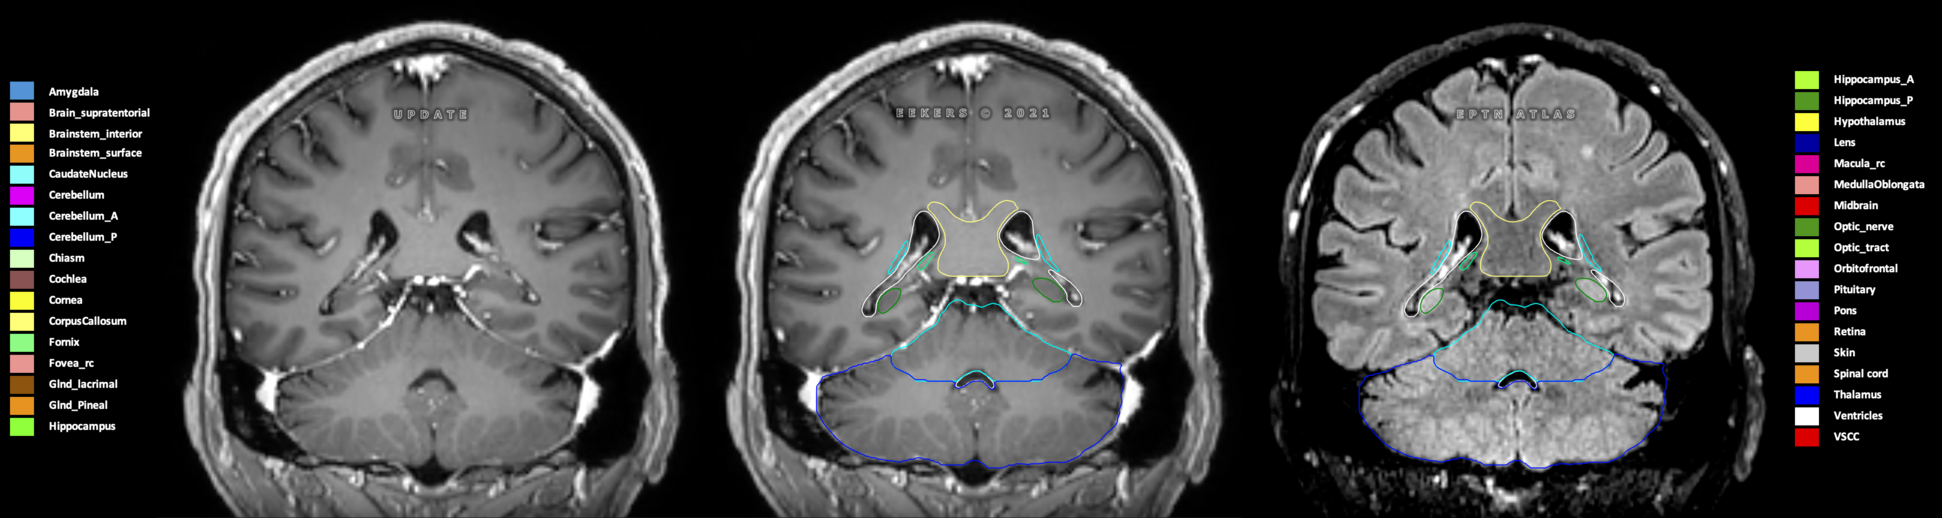

Eekers et al. have published an international neurological atlas for contouring of organs at risk in consensus with the European Particle Therapy Network (EPTN) in 2018 and an update in 2021. The purpose of this consensus atlas is to decrease inter- and intra-observer variability in delineating OARs relevant for neuro-oncology.

Included are all OARs known to be relevant for radiation-induced toxicity in neuro-oncology: brain, brainstem (midbrain, pons, medulla oblongata), chiasm, cerebellum (anterior & posterior), cochlea, cornea, hippocampus (anterior & posterior), hypothalamus, lens, lacrimal gland, optic nerve, pituitary, skin, and vestibular & semicircular canals. To further facilitate research on cognition, vision and radiological changes after irradiation of the brain, potential clinically-relevant OARs are included: amygdala, caudate nucleus, cerebellum (anterior & posterior), corpus callosum, fornix, macula, optic tract, orbitofrontal cortex, periventricular space (PVS), pineal gland, and thalamus.

Three-dimensional delineation of the 25 consensus OARs for neuro-oncology are shown on CT (WW/WL 120/40, 3000/600), 3T MR images, (T1Gd, T2FLAIR 1mm) and 7T MR (MP2RAGE 0.7 mm). All are presented in transversal, sagittal and coronal view.